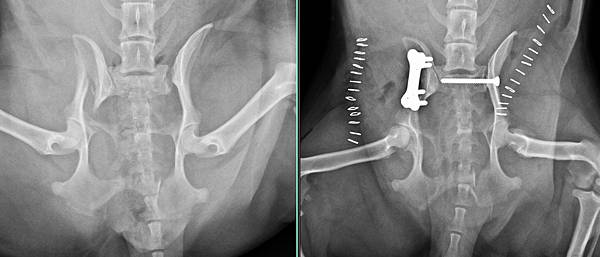

妹妹是位很調皮的臘腸姑娘

有天偷跑出去被車撞

來找小譚醫師處理骨折的骨盆與脫臼的腸薦關節

經過手術後

妹妹恢復很好

再休息一陣子就可以跑跳了